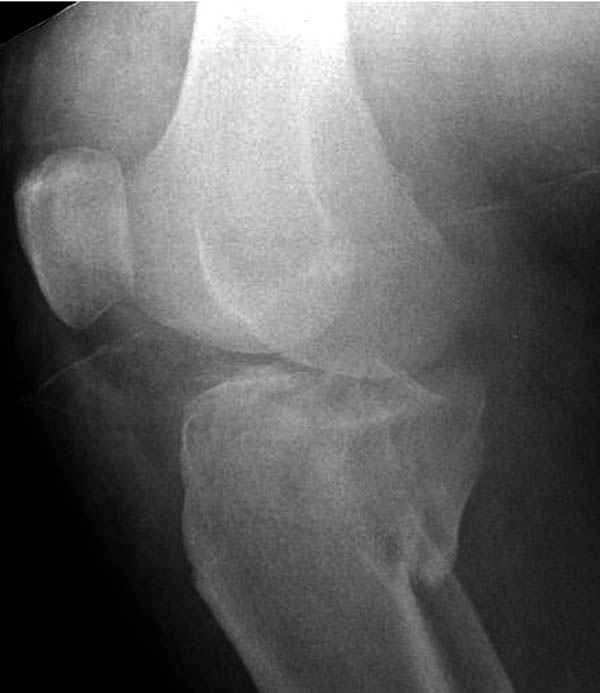

Трудно поверить, что разрекламированная Ортопедическая школа Восточной Украины позволяет такие странные снимки? На прямом снимке сохранен общий контур плато, но не известна судьба импрессии суставной поверхности. На полубоковой?, оставлен без репозиции задне-медиальный отдел, и навряд ли после такой фиксации можно удовлетвориться результатом.

На представленных предоперационных срезах КТ огромный задне-медиальный фрагмент расположен больше кзади, чем медиально. Для планирования, кроме поперечных срезов, надо ориентироваться на корональные срезы, которые укажут топографию верхушки медиального фрагмента.